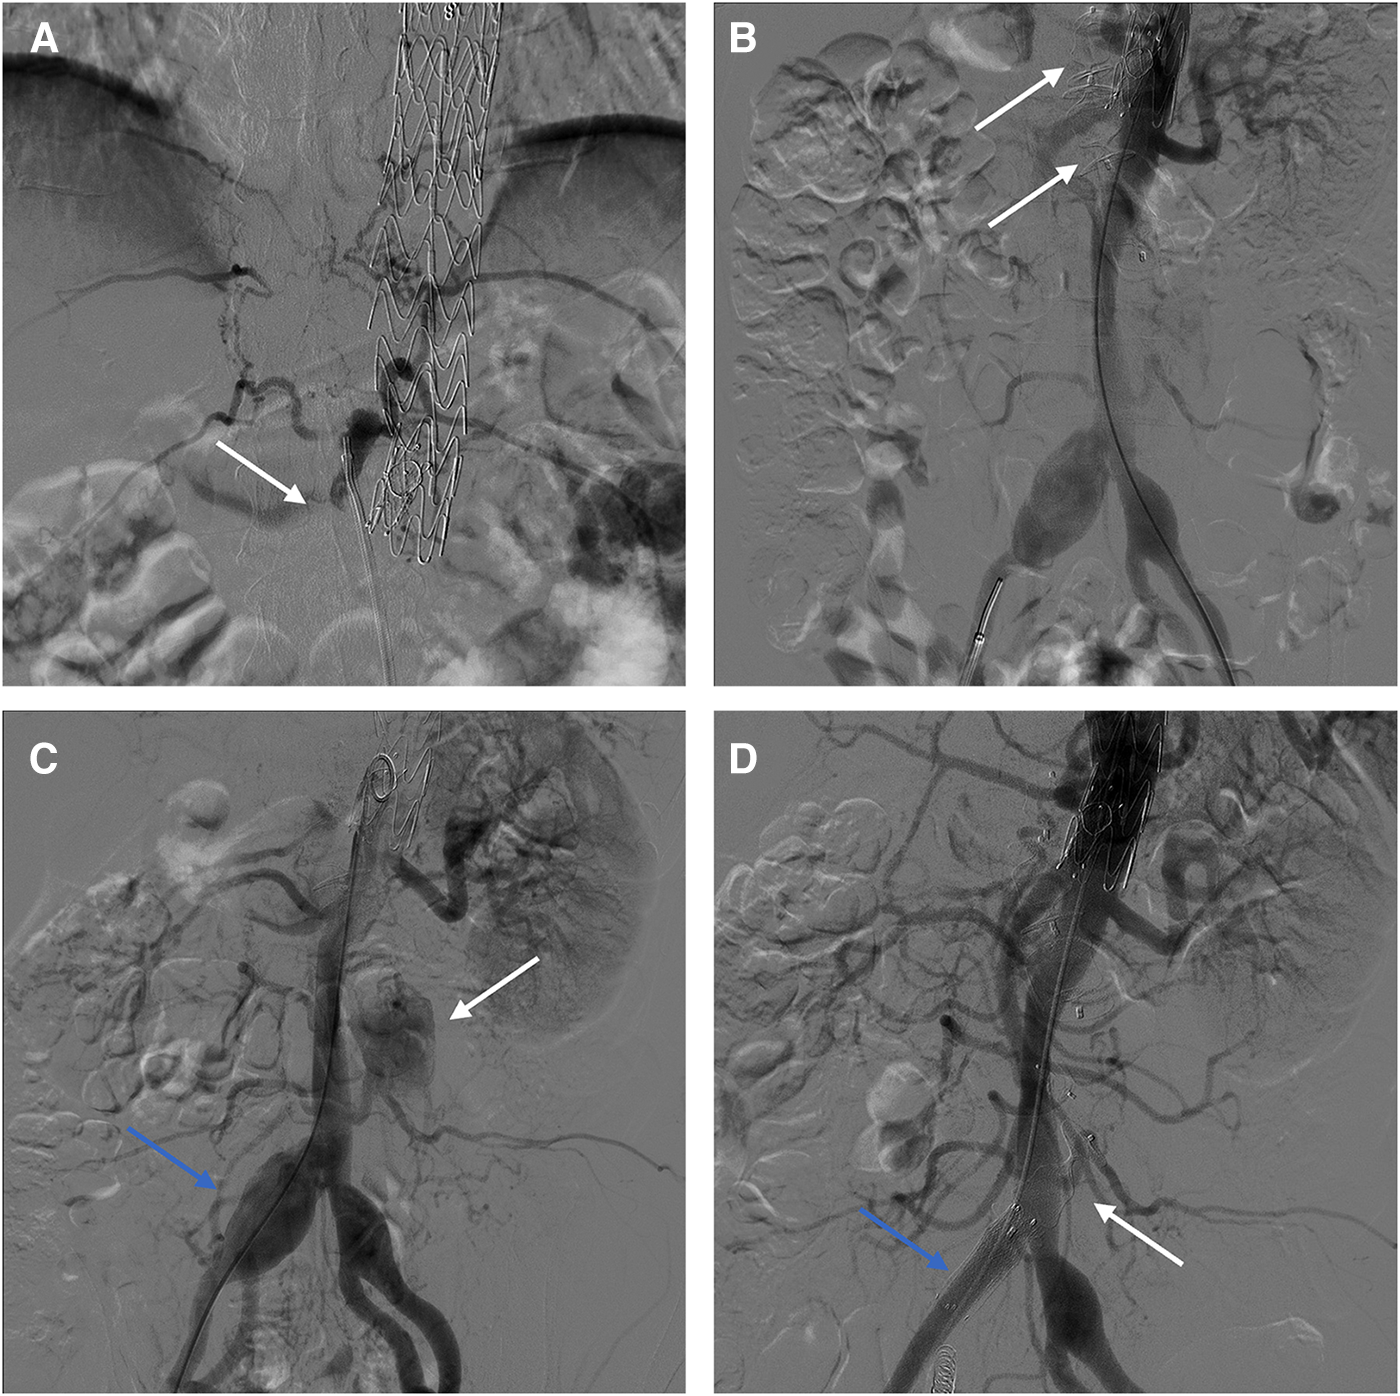

Case 3: A 38-year-old male underwent F/B-EVAR for type B aortic dissection 2 years ago. Postoperative CTA follow-up: The patient has a post-dissection abdominal aortic aneurysm, with a maximum diameter of approximately 52 mm. The intimal tears are located at the level of the infrarenal abdominal aorta and the right common iliac artery respectively. All visceral arteries originate from the true lumen (Supplementary Figure S2A).

Procedure 1: Under local anesthesia, the false lumen was accessed via a tear in the right iliac artery (Figure 4A). Subsequently, AVP II with diameters of 16 mm, 20 mm, and 22 mm were placed to embolize the false lumen (Figure 4B). Intraoperatively, angiography revealed that several lumbar arteries arose from the false lumen. Since the therapeutic goal had been attained, the procedure was terminated to prevent acute spinal cord ischemia. The second phase of the surgery is scheduled to take place in a few months. Follow-up CTA revealed persistent blood flow in the mid to distal false lumen of the abdominal aorta, with distal narrowing, indicating the possibility of re-embolization therapy (Supplementary Figures S2B,C). Procedure 2: Under local anesthesia, right femoral artery access. Angiography showed post-dissection aortic aneurysm formation, and the tear was located in the infrarenal abdominal aorta and right iliac artery (Figure 4C). The 8F guiding catheter passed through iliac artery tear into false lumen, then entered true lumen via abdominal aorta tear. Placed 8 mm × 6 mm AVP II at tear site. A 20 × 16 mm AVP II was inserted into the stenosed false lumen, and Interlock mechanically detachable coils (Boston Scientific, Natick, MA, USA) was used to embolize the right internal iliac artery. Subsequently, a 13 mm × 50 mm Viabahn stent (W. L. Gore & Associates, Flagstaff, AZ, USA) and a 10 mm ×80 mm Fluency stent (Bard, Temple, AZ, USA) were placed in the right iliac artery to block the tear. Intraoperative angiography reveals patent visceral arteries and no false lumen opacification (Figure 4D). The 6-month postoperative CTA examination showed stable positions of the AVP and stent graft, with complete thrombosis in the false lumen. The abdominal aorta diameter decreased from 52 mm to 47 mm, while the true lumen increased from 24 mm to 28 mm (Supplementary Figure S2D).

Figure 4

(A) Intraoperative angiography showed abdominal aortic false lumen opacification. (B) AVPs were inserted into the false lumen. (C) Opacification of false lumen in infrarenal aorta (white arrow); Aneurysmal dilatation of right iliac artery (blue arrow). (D) Final intraoperative angiography showed the AVP (white arrow) and the stent (blue arrow).